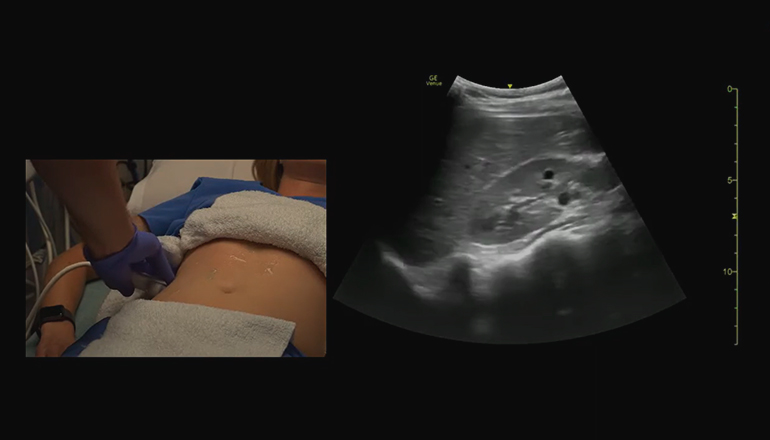

УЗИ брюшной полости на дому проводится также, как в клинике. Пациент снимает одежду по пояс и ложится. Врач наносит на зону сканирования гель и с помощью абдоминального датчика проводит исследование. Оно длится примерно 30 минут. Затем доктор заносит показатели в протокол и выдает его пациенту на руки.